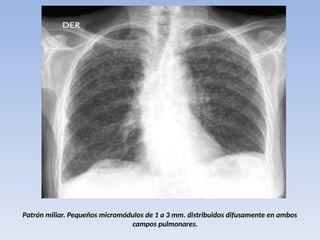

TUBERCULOSIS MILIAR

• resultado de la diseminación hematógena

• fases iniciales, normal. una semana

después ,presencia de un halo difuso, mal

definido en ambos pulmones y

posteriormente la imagen típica de nódulos

pulmonares miliares bien definidos.

• Afectación es de todos los campos

pulmonares, existen adenopatías hiliares

Patrón miliar. Pequeños micromódulos de 1 a 3 mm. distribuidos difusamente en ambos

campos pulmonares.